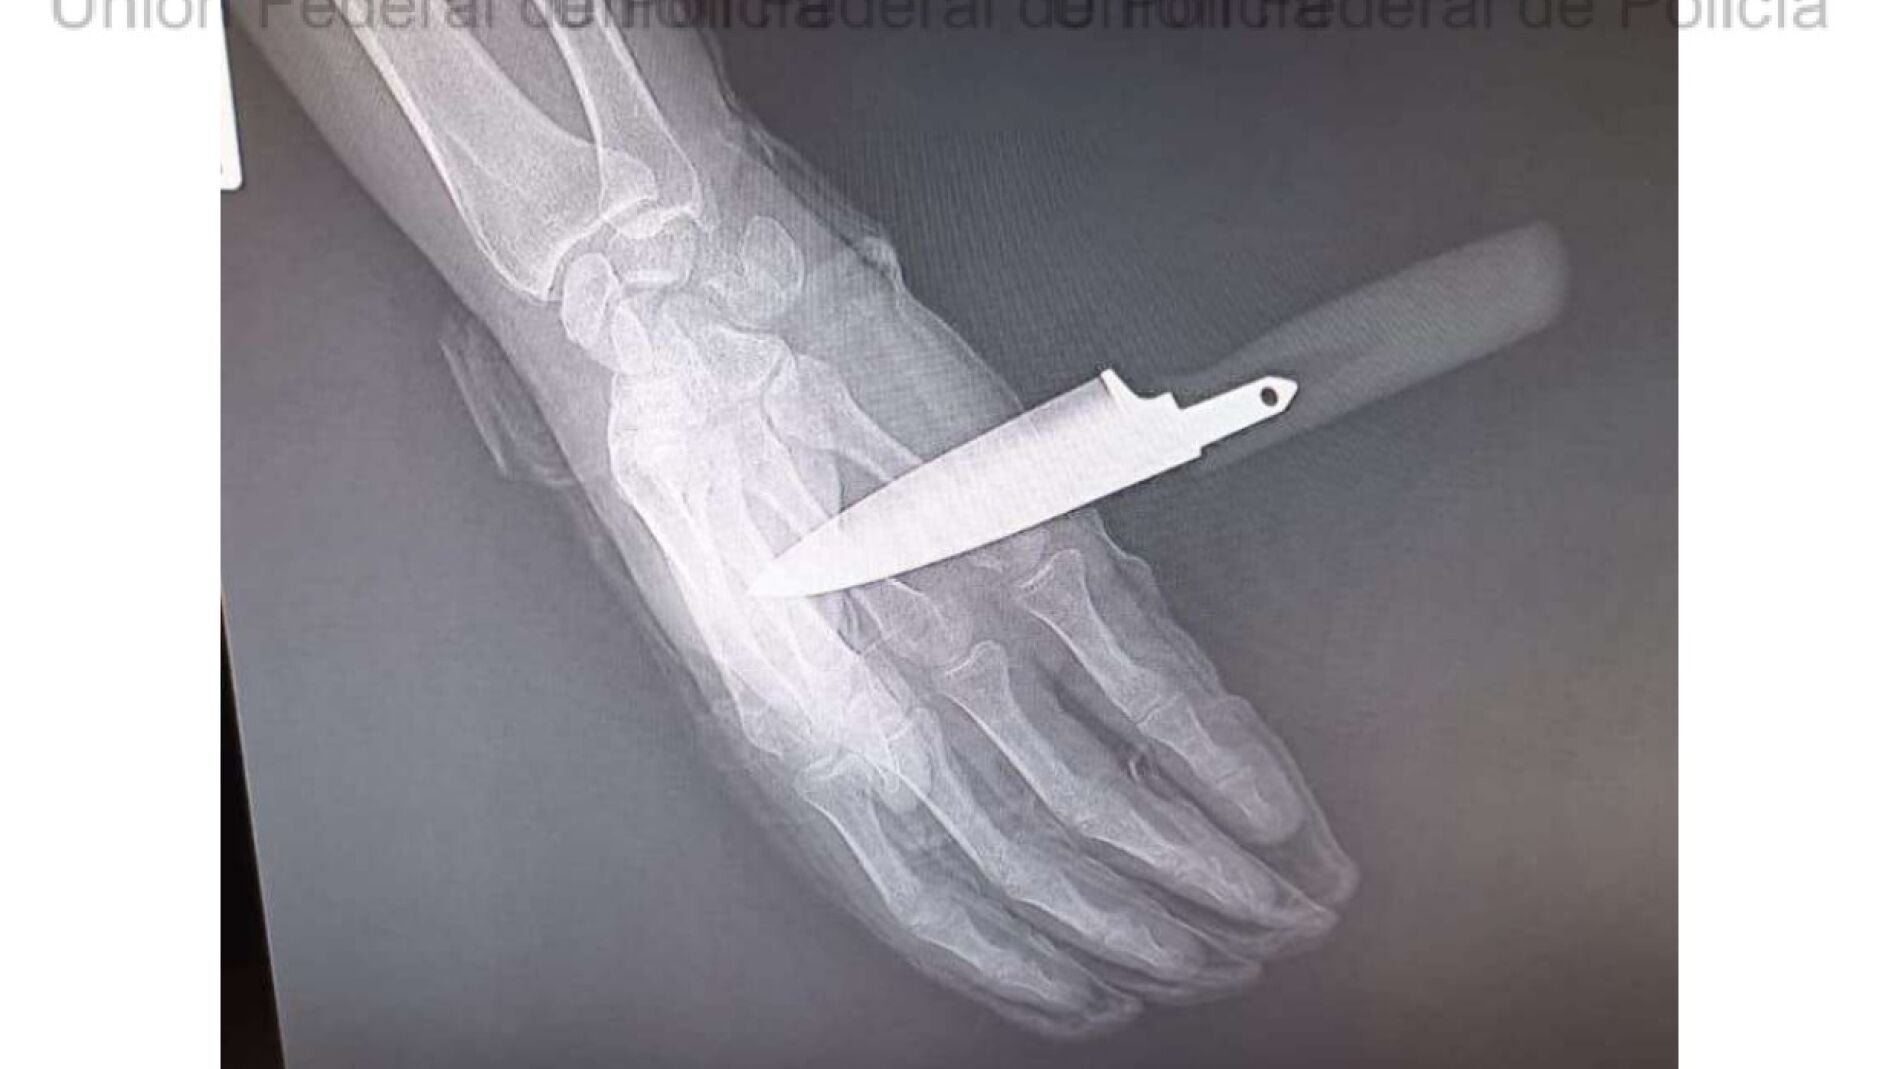

Herido por arma blanca un policía al intervenir en una disputa familiar en Baza (Granada)

El hijo de la mujer arremetió "violentamente" contra uno de los agentes...